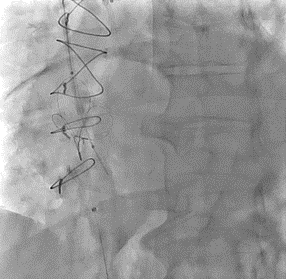

After the right transjugular puncture and introducer implantation, the coronary sinus (CS) was catheterized (Figure, A; Video 1). A CSR was advanced to the targeted implantation site in the mid-segment of the CS. The guiding catheter was then retracted, and the balloon was inflated to expand the CSR at the implantation site. After deflation, the balloon was retrieved. During the extraction of the deflated balloon, under fluoroscopy, we observed device migration into the right atrium while being attached at the tip of the catheter (Figure, B; Video 2). To snare the reducer, a 14-French sheath was advanced in the right femoral vein. We attempted to keep the wire inside the stent, but the prothesis migrated to the left pulmonary artery without the possibility of recovering it using the lasso technique (Figure, C; Video 3). We decided to implant a second CSR more distally in the CS (Figure, D; Video 4).

Though uncommon, migration during implantation is one of the most-reported complications of CSR implantation.1 If the snare technique fails to capture the embolized prothesis, or if the prothesis migrates to a distal branch of a pulmonary artery, the CSR may be left in place distally.